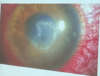

Como se ve la queratitis por pseudomonas

Signos que podemos encontrar en la exploración oftalmológica en queratitis bacteriana

Inyección ciliar e Hipopion